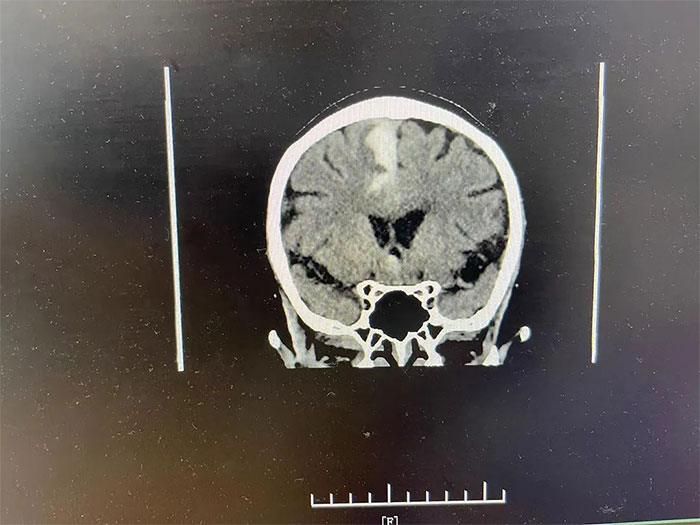

▲ 入院检查颅内仍有出血活动

更令人不安的是,CT检查显示,吴阿姨右侧大脑顶叶出血灶较前变化不明显,提示仍有出血活动,若不及时进行干预,随时都有“决堤”的可能,不仅影响神经功能恢复,病情还可能因之进一步恶化,甚至危及生命。

▲ 通过治疗,出血已基本吸收